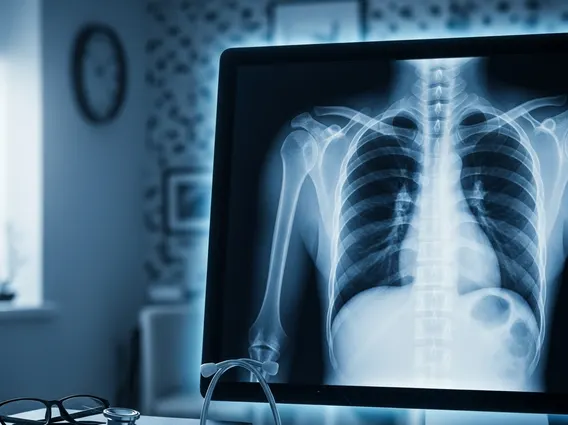

Chest X Ray

A Chest X Ray is a common imaging test that uses a small amount of radiation to create pictures of the chest, including the heart, lungs, blood vessels, airways, and the bones of the chest and spine. It’s a quick and non-invasive way for doctors to assess the health of these vital organs and structures.

A Chest X Ray, also known as a chest radiograph, is a fundamental diagnostic tool in medicine. It is an imaging technique that utilizes X-rays to generate two-dimensional images of the organs and structures inside the chest cavity. This includes the lungs, heart, large blood vessels, diaphragm, and the bones of the chest wall and spine. The primary purpose of understanding what is Chest X Ray is to help physicians detect, diagnose, and monitor various medical conditions affecting these areas, providing crucial insights into a patient’s health without invasive procedures.